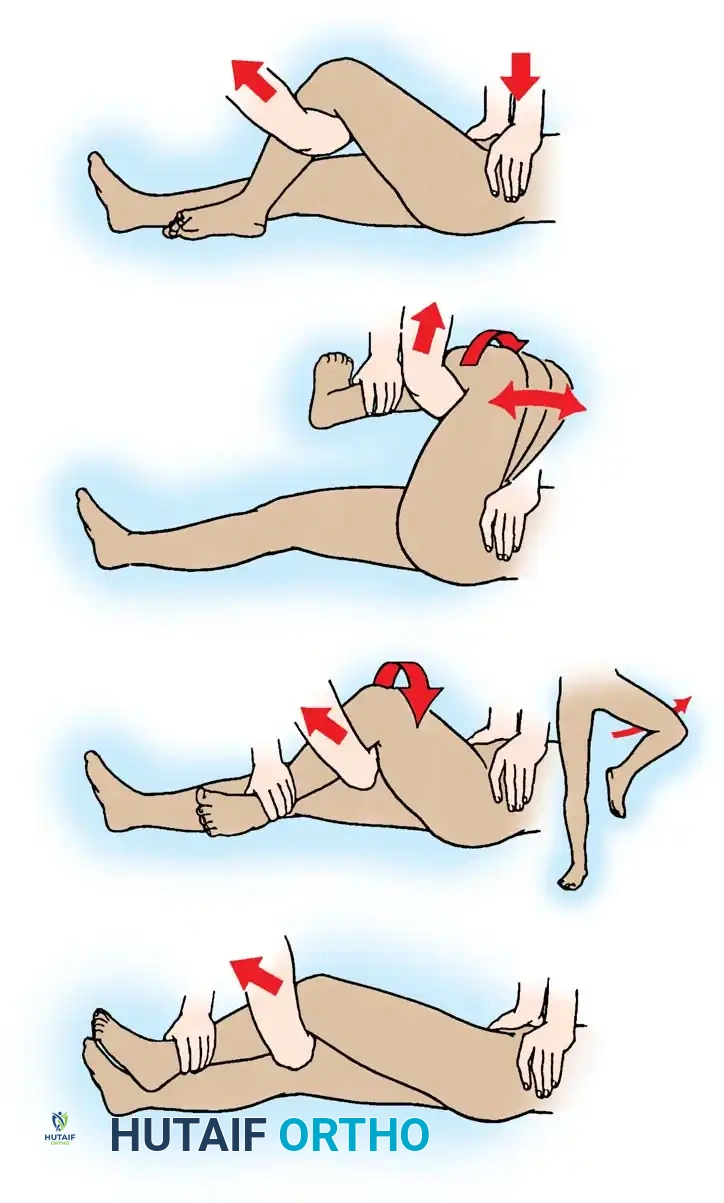

The Allis maneuver is the most commonly utilized technique due to its safety and efficacy in the supine patient.

- The patient is positioned supine. An assistant firmly stabilizes the pelvis by applying downward pressure on both anterior superior iliac spines.

- The surgeon applies steady, inline longitudinal traction in the direction of the deformity.

- While maintaining traction, the surgeon slowly flexes the patient's hip and knee to 90 degrees.

- Gentle internal and external rotation of the hip is applied to clear the posterior acetabular lip until a palpable "clunk" indicates concentric reduction.

Fig. 52-48 (Part 1) Allis reduction maneuver for posterior dislocation of the hip. Initial inline traction and flexion.

Fig. 52-48 (Part 2) Allis reduction maneuver. Application of rotational forces to lever the femoral head into the acetabulum.

The Gravity Method of Stimson

The Stimson method is highly effective and minimally traumatic but requires the patient to be prone, which is often contraindicated in polytrauma patients with spine or thoracic injuries.

- The patient is placed prone on a stretcher with the affected lower extremity hanging off the edge.

- An assistant stabilizes the pelvis.

- The hip and knee are flexed to 90 degrees. The surgeon grasps the proximal calf and applies a steady, downward longitudinal force.

- Gentle rotation aids in guiding the head back into the acetabulum.

The Bigelow Maneuver

The Bigelow maneuver utilizes the intact iliofemoral ligament as a fulcrum. It is more complex and carries a slightly higher risk of iatrogenic femoral neck fracture if performed forcefully.

- With the patient supine and pelvis stabilized, the surgeon grasps the ankle and places their opposite forearm beneath the flexed knee.

- Longitudinal traction is applied, followed by flexion of the hip to 90 degrees in an adducted, internally rotated position.

- The femoral head is levered into the acetabulum through a sweeping motion of abduction, external rotation, and extension.

The East Baltimore Lift

This technique is excellent for minimizing surgeon fatigue and back strain, utilizing the combined strength of two providers.

- The patient is supine. The surgeon and an assistant stand on opposite sides of the affected limb.

- The patient’s hip and knee are flexed to 90 degrees.

- Both providers place their arms under the patient's proximal calf, resting their hands on each other's shoulders.

- By simultaneously standing up from a squatted position, they apply powerful, controlled upward traction while a second assistant stabilizes the pelvis.